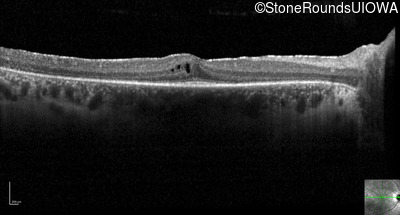

Optical Coherence Tomography - Right -

20/20 -1

Exemplar / OCT Stack